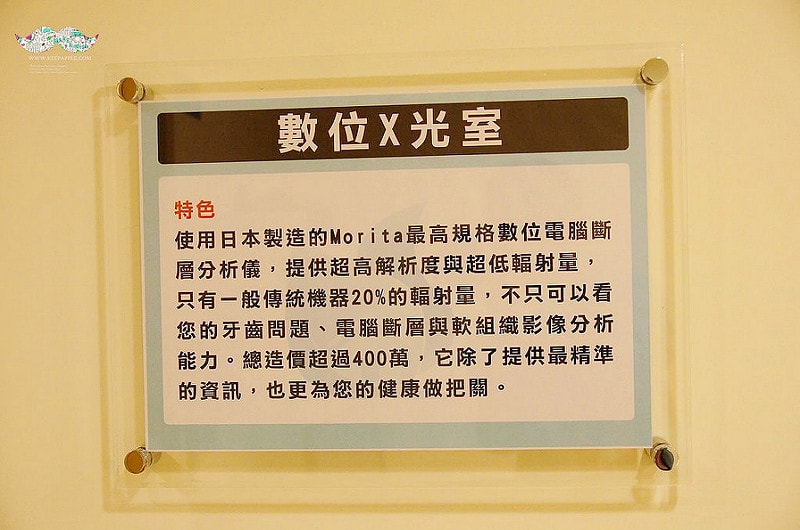

我的話是有先來做過一次全口的X光照射

這是病人來都要先做的事情

也比較好讓院方知道牙齒的問題在哪兒